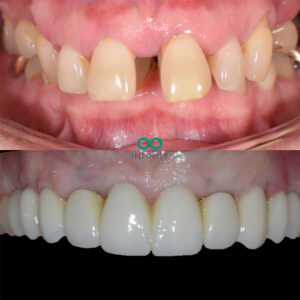

I completed the treatment for our patient this week to replace almost all of her upper teeth. She presented to our clinic with most of her upper teeth failing due to advanced periodontal disease. This is a severe form of gum disease that had resulted in significant bone loss which resulted in these teeth becoming loose.

After the 6 months had passed, we carefully sculpted her gum line with all the volumous gum graft that had now worked and fully healed. The contours we had created were carefully designed to mimic her natural smile design that we planned using our digital smile desgin programmes. Following this careful gum sculpting process, we made a truly bespoke implant bridge that looked and felt as natural as is possible. The patient was delighted and we were especially proud of the fit between the gums and the implant teeth. That new gum line was healthy, natural and therefore very easy for the patient to clean and maintain daily with a normal electric toothbrush.

That is the thing with gum contouring – it enables us to provide natural teeth. Natural is important because it often means it will last longer and be more ‘natural’ to maintain too.

Another truly life changing smile. Another smile that just looks normal!